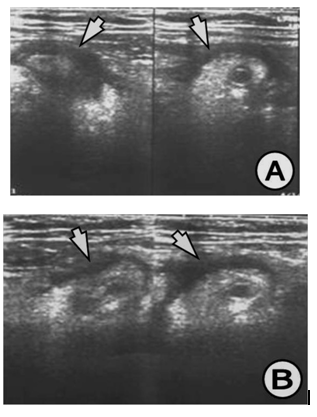

The appendix on US study is demonstrated by: hypo echoic lumen, hyper echoic mucosa, iso echoic lamina propria, hyper echoic submucosa, hypo echoic muskularis and hyper echoic serosa. The increased size of the appendix is a sign for phlegmonous or gangrenous appendicitis (Figure 1). The present appendicolith is demonstrated as hyper echoic mass that fills in the lumen and gives acoustic shadow (Figure 2B). When the appendicolith should be visualized, the wall thickness and the compressibility are not the features for making the diagnosis of acute appendicitis. The gangrenous appendicitis has changes in echogenity in all layers and the same are with the uniform echogenity and cannot be distinguished (Figure 3A). If the ill defined or hypo echoic mass is seen that surrounds the appendix that presents the periappendiceal inflammation (Figure 4). The ill defined appendiceal wall is suggestible, but not diagnostic for the periappendiceal process. The fluid presence into the appendiceal surrounding, with appendiceal wall echogenity changes is US feature for perforation (Figure 3B). The positive lymph nodes are oval hypo echoic and they don’t change the shape on compression.

Figure 1 (A) Appendix increased in size, 17 mm in diameter, thickened wall greater than 6 mm, (B) Appendix with widened lumen with dense contents, with 18 mm in diameter and thickened wall greater than 5 mm. US finding for appendiceal phlegmon.

Figure 2 (A) Appendix increased in size, thickened wall, widened lumen, US finding for appendiceal phlegmon, (B) Clearly visualized appendicolith into the lumen of the appendix, which is with thickened wall and widened lumen, US finding for appendiceal phlegmon.